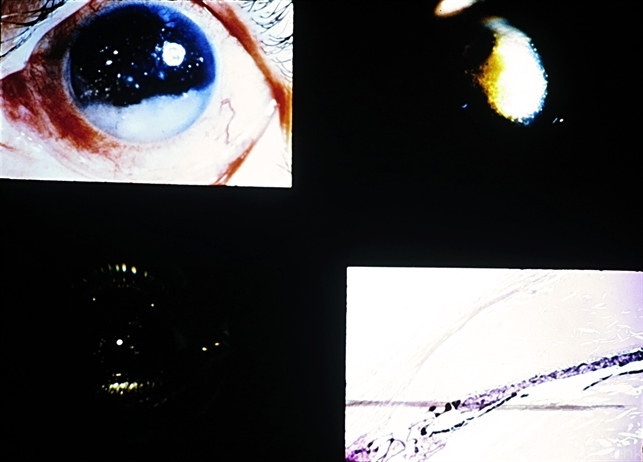

- cholesterolosis bulbi, hemophthalmos

- Cholesterosis bulbi (hemophthalmos). When in the anterior chamber, these crystals have a whitish or yellowish-gold appearance. Upper right and lower views are of the same case (E.P. No. 31377) and show cholesterol in the anterior and posterior chambers.